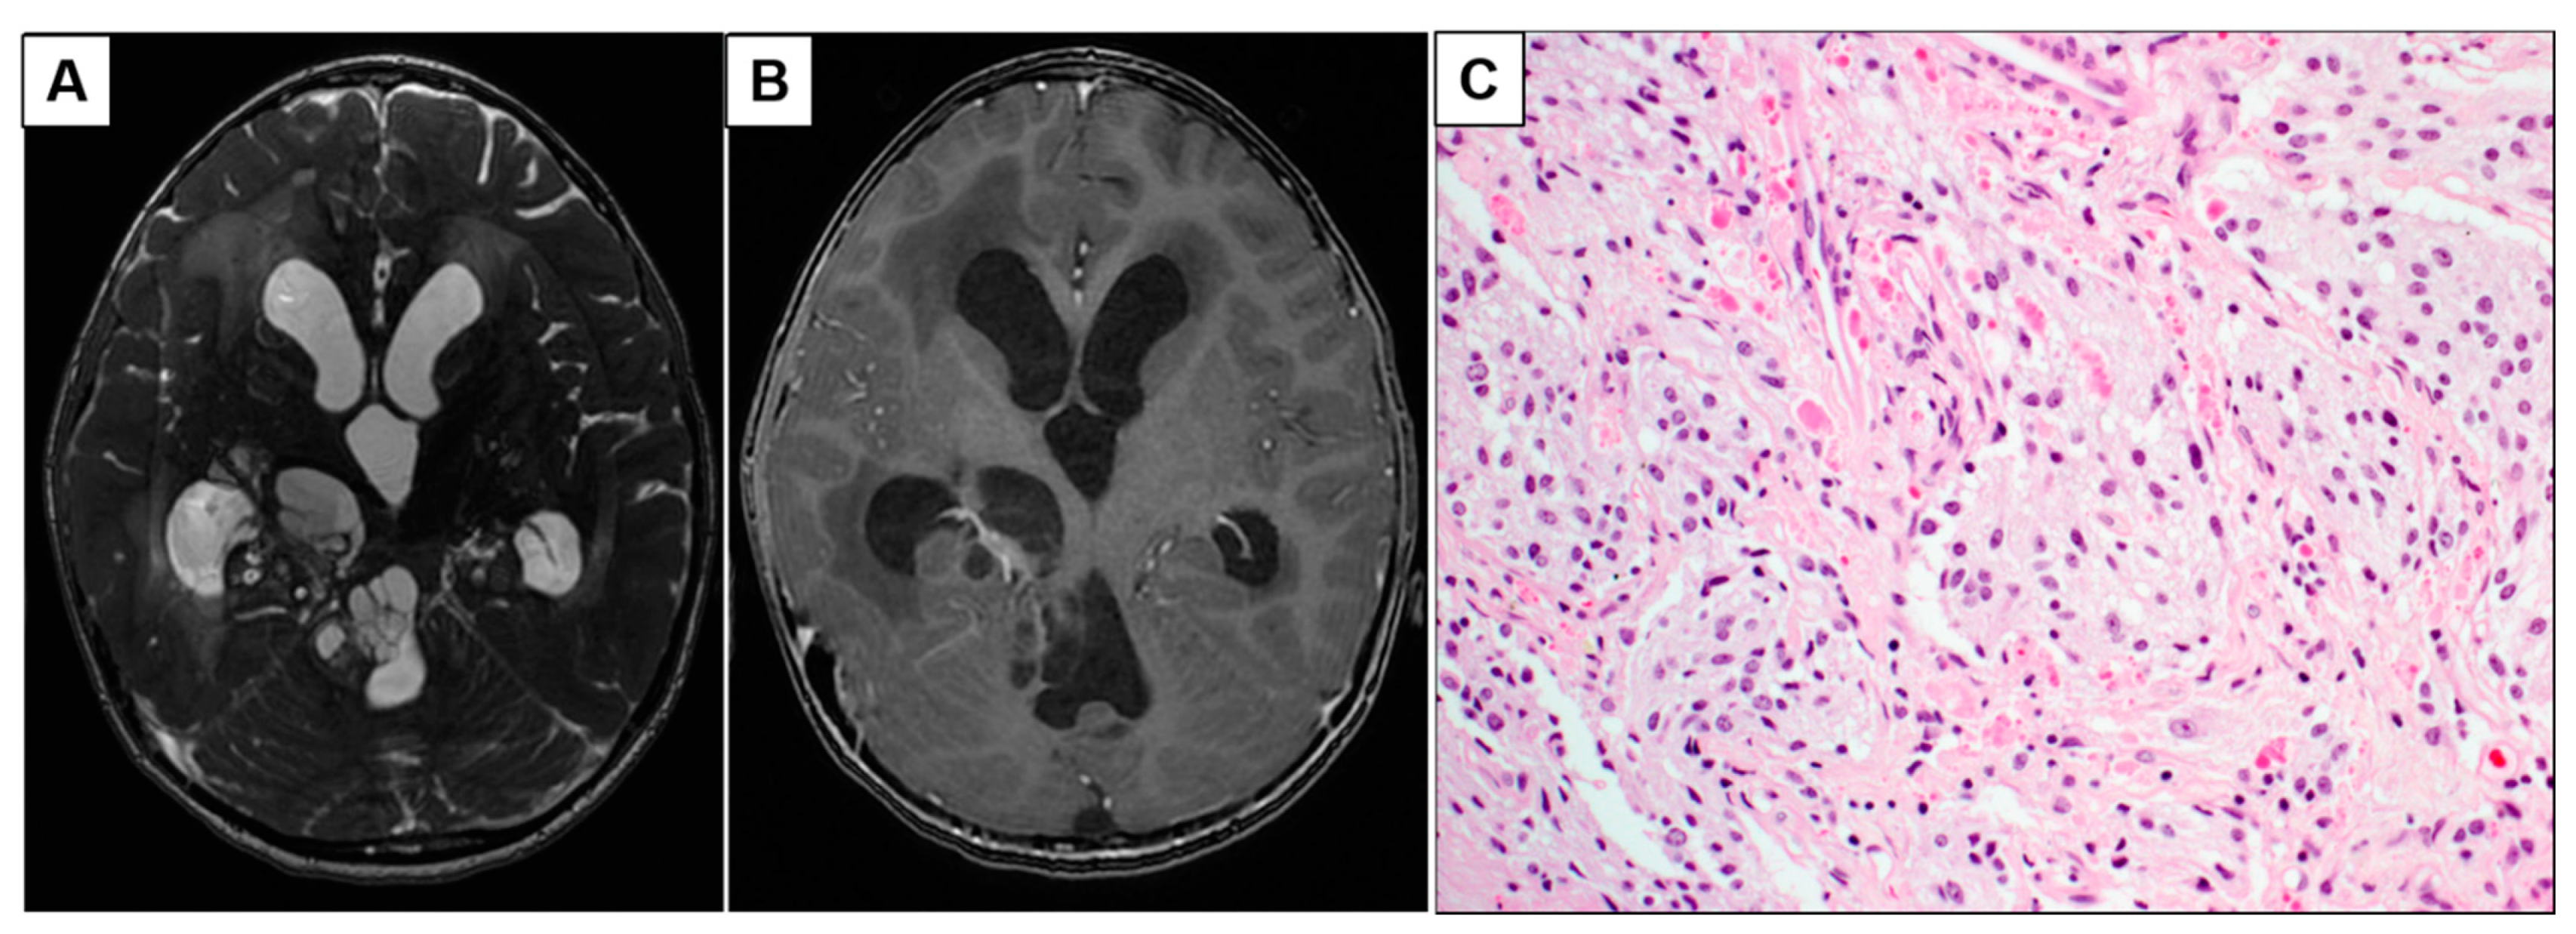

3.1.2. Patient 5: Progressive Intraventricular PCA with Leptomeningeal Disease